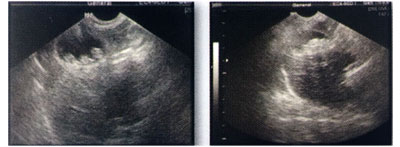

우연히 뢴트겐을 찍었을 때 담낭슬러지(담즙의 저류)가 발견된 사례이다. (사진1)

혈액검사에 의해 간효소치(ALT)의 상승(※간기능 저하)이 판명되었기에, 증상 확인을 위해 CT도 찍어(사진1좌하단), 이대로라면 파열의 위험성도 있다고 판단하여 쓸개 적출수술을 실시했다.